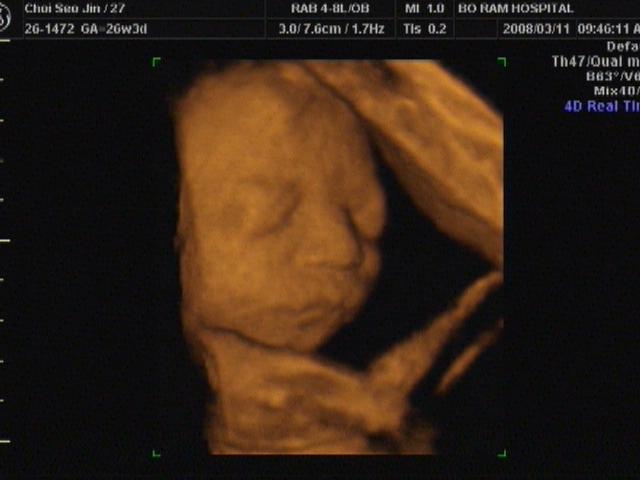

자궁경관무력증으로 21주에 아기보내고 작년 다시와준아기

원장님에 쉬로드카수술로 지금 건강하고 ...